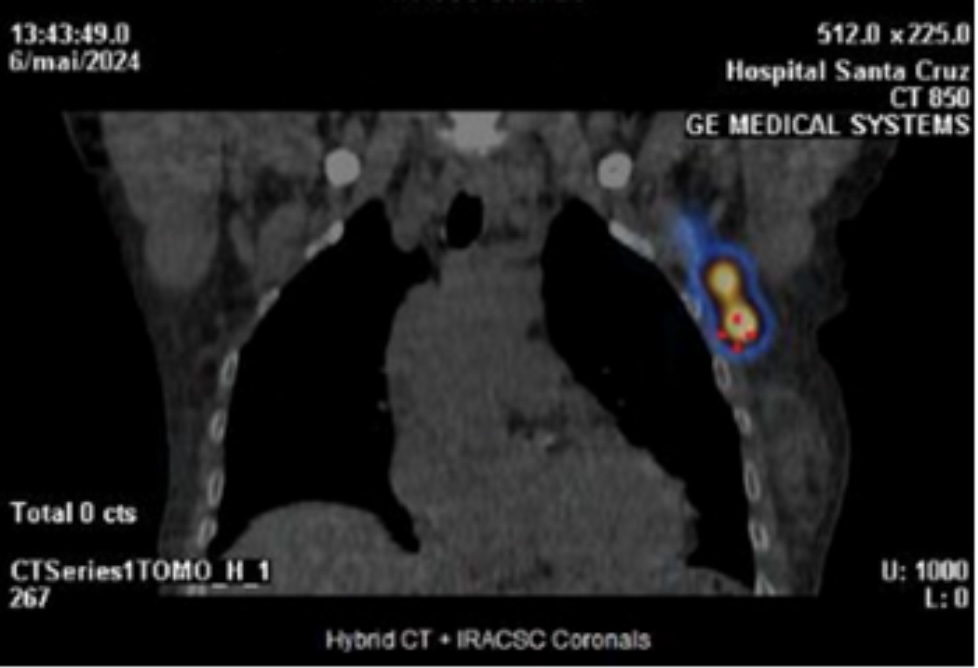

Preoperative lymphoscintigraphy scan revealed a drainage route to the sentinel lymph node in the contralateral axilla (Fig 1 and 2). In May 2024, she went under right simple mastectomy, right axillary lymph node dissection (“no show” of sentinel lymph node), and left sentinel node biopsy.

Fig. 1 - SPECT/CT images show a high intensity deposit in the left axilla, which was considered the sentinel node of the right breast cancer - coronal cut